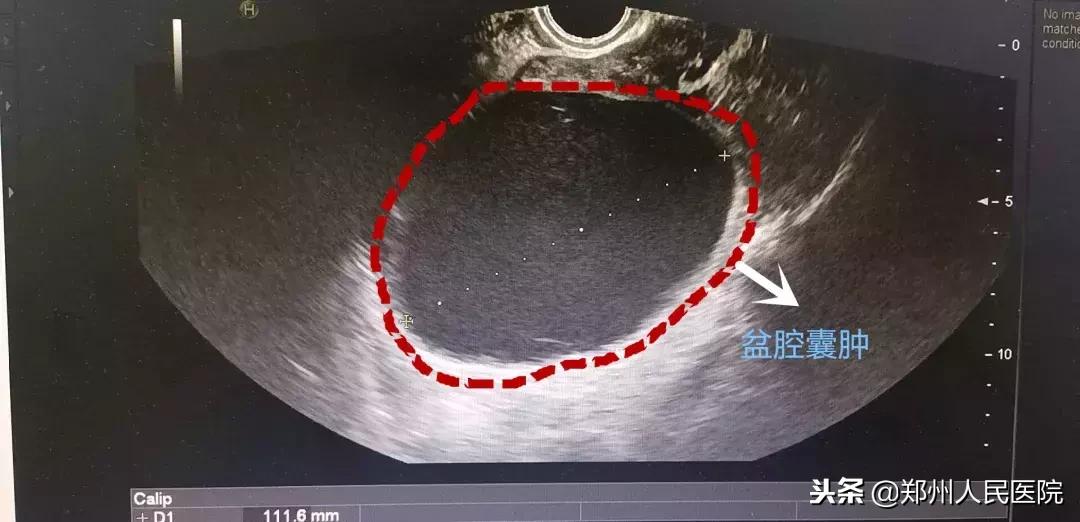

结果发现汤女士的盆腹腔内可触及一大小约12cm×12cm×10cm的包块,上界*平近**脐,活动差,深压痛。妇科超声结果提示:左侧附件区探及范围约93mm×84mm×112mm无回声,内透声欠佳,可见密集点状回声,边界清。

根据多年的临床经验,郭伟平主任判断汤女士高热的源头就是这个拳头大小的包块,极有可能是盆腔脓肿引起的,决定立即手术治疗。